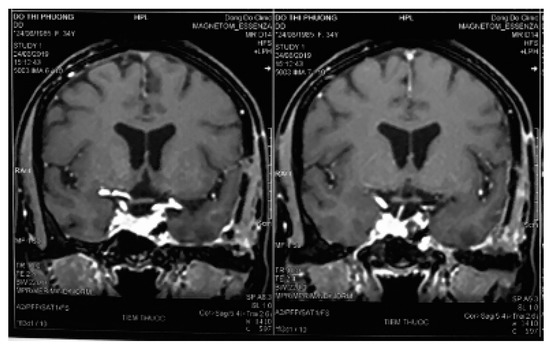

Figure 3.

Two-day postoperative computed tomography scan images.